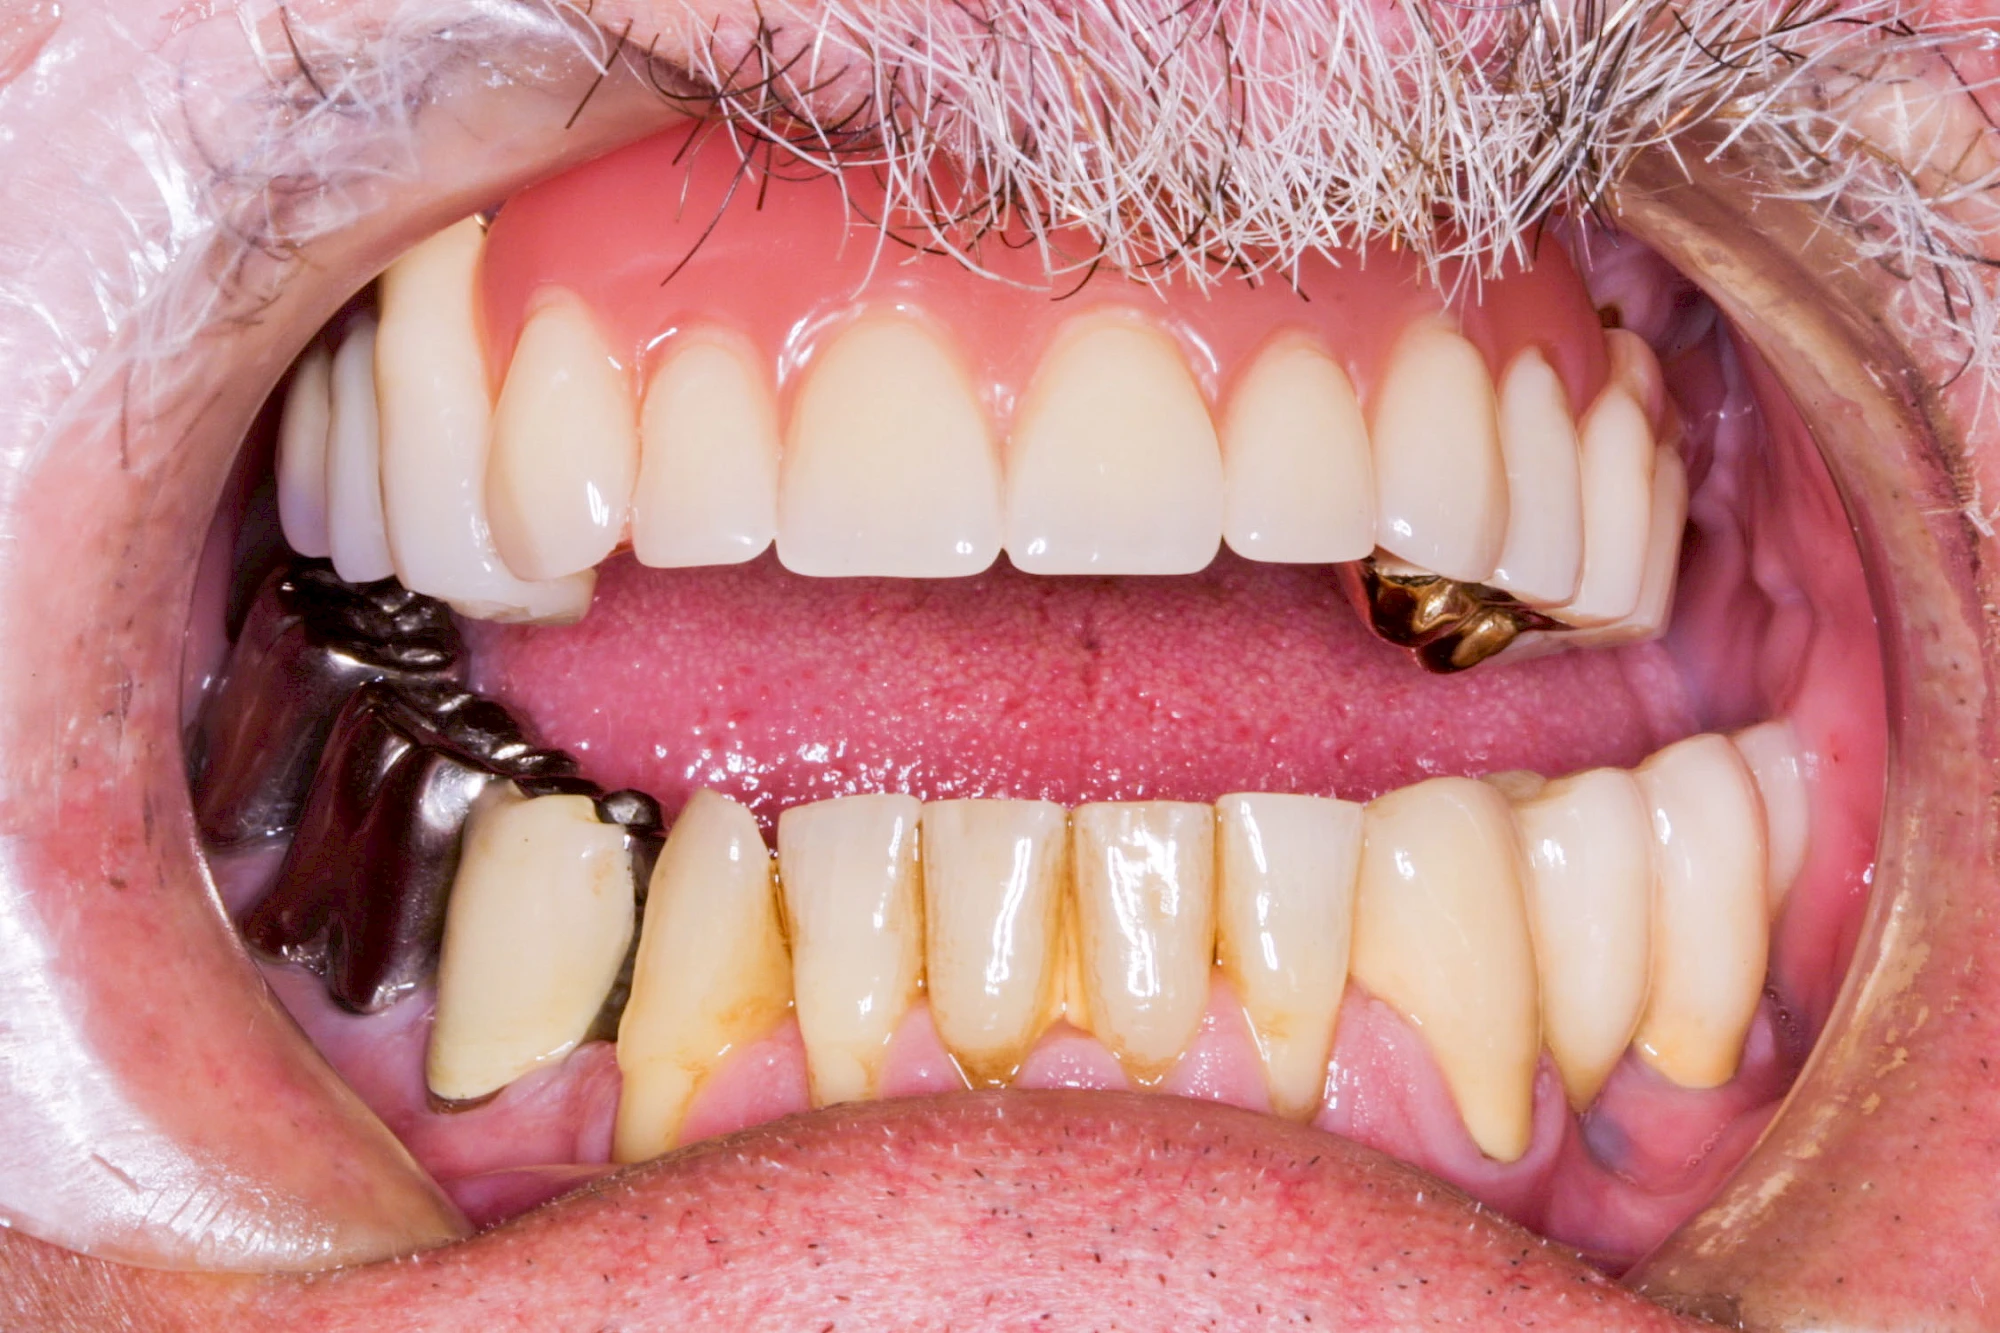

Gehen die Zähne verloren, baut häufig auch der Kieferknochen ab (Knochenschwund). Die Geschwindigkeit und das Ausmaß des Knochenschwundes ist von vielen Faktoren abhängig. Neben der genetischen Veranlagung spielen auch Überbelastungen in Folge, z. B. bei ständigem Knirschen oder Pressen, eine Rolle. Auch wenn Zahnprothesen Tag und Nacht getragen werden, kann die ständige Belastung der Schleimhäute und des Knochens den Knochenschwund beschleunigen.

Aber Achtung: Manche Menschen fühlen sich ohne Zahnprothesen unwohl. Zudem kann es passieren, dass Zahnprothesen (wenn noch eigene Zähne vorhanden sind) nicht mehr passen. Dies gilt vor allem dann, wenn diese Zahnprothesen nicht nur über Nacht, sondern für einen längeren Zeitraum nicht mehr getragen werden.

In seltenen Fällen schwindet nur der Knochen, aber nicht die bedeckenden Schleimhäute. In diesen Fällen spricht man von einem sogenannten "Schlotterkamm".